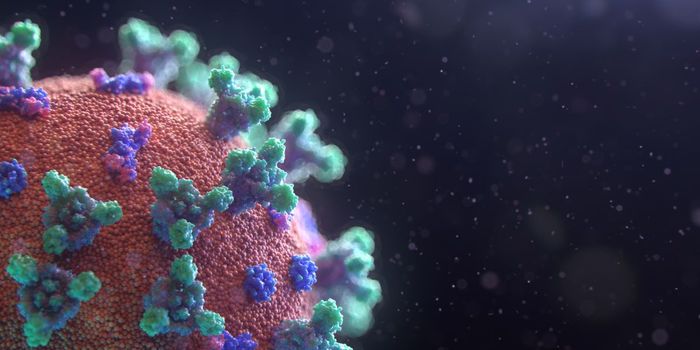

MAR 17, 2020ImmunologyStructurally, SARS-CoV-2 (the virus that causes COVID-19) are spherical shells consisting of a lipid membrane, with a co ...

MAY 04, 2020MicrobiologyThe COVID-19 pandemic has spread around the world and there is still no available treatment or a vaccine. Prevention rem ...

MAR 19, 2020Drug Discovery & DevelopmentAs panic is spreading over the novel coronavirus, the time is ripe for both misinformation and disinformation to thrive. ...

JUL 09, 2020ImmunologyThe number of confirmed COVID-19 cases worldwide is steadily approaching 12 million. Meanwhile, despite accelerated time ...